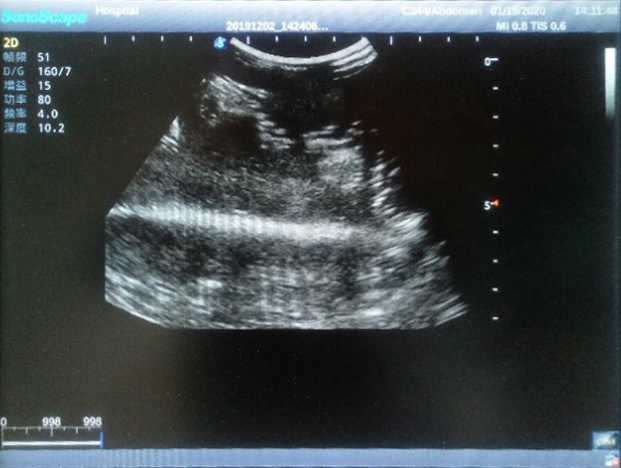

4) Biomimetic material allowing users to see clear and real normal tissues and space-occupying lesions that are hyperechoic, hypoechoic and isoechoic as they would see in the clinical environment